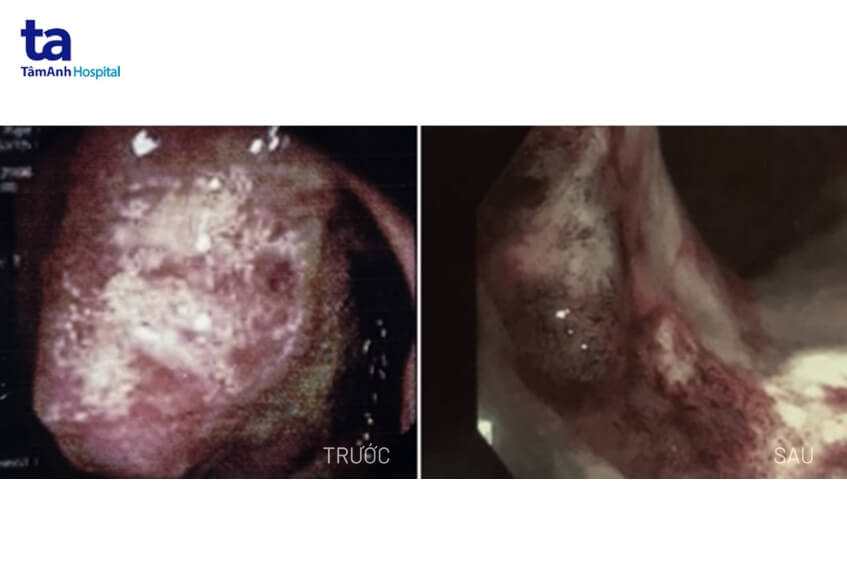

Kết quả nội soi đại trực tràng ghi nhận có một tổ chức khối u lớn cách rìa hậu môn 10cm, chiếm gần hết chu vi lòng trực tràng (nguyên nhân dẫn tới tình trạng khuôn phân dẹt, đại tiện khó); bề mặt khối u chia múi nham nhở, dễ chảy máu. Ngoài ra, bệnh nhân còn có nhiều hạch to ở ổ bụng, nhiều hạch thượng đòn 2 bên, hạch trung thất, may mắn khối u chưa di căn đến phổi và não. Bệnh nhân được chẩn đoán bị ung thư trực tràng giai đoạn IV, thuộc loại ung thư biểu mô tuyến xâm nhập.

Theo bác sĩ Khiêm, sau 6 đợt điều trị hóa chất, khối u lớn ở phần đại tràng đã thu nhỏ còn 6mm so với kích thước ban đầu là 15mm, hạch to nhất cũng giảm từ 30x22mm còn 5x7mm, bờ gồ nhẹ, đèn nội soi đã đi qua được. Người bệnh không gặp tác dụng phụ từ các đợt hóa trị, tăng cân tốt, ăn ngủ được, đại tiện hoàn toàn bình thường và không còn hạch cổ.